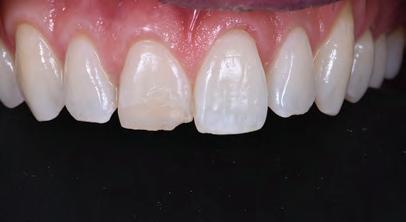

A 30-year-old patient, with a negative medical history, came to the clinic requesting the replacement of the previous composite reconstruction performed 10 years earlier following a trauma to UR1.

On clinical examination, UR1 was responsive to viability testing, and did not present periapical lesions on the radiograph performed on the same day (Figure 1). UR1 was discoloured and in a more palatal position than the contralateral central UL1 (Figure 2). The aesthetic analysis highlighted an asymmetry of the gingival zenith between UR1 and UL1. Through the use of a periodontal probe, after plexus anaesthesia, the altered passive eruption of the type IA junctional epithelium was confirmed according to the classification of Coslet et al. (Figure 3).

FIGURE 2: Discolouration and palatal position of UR1.